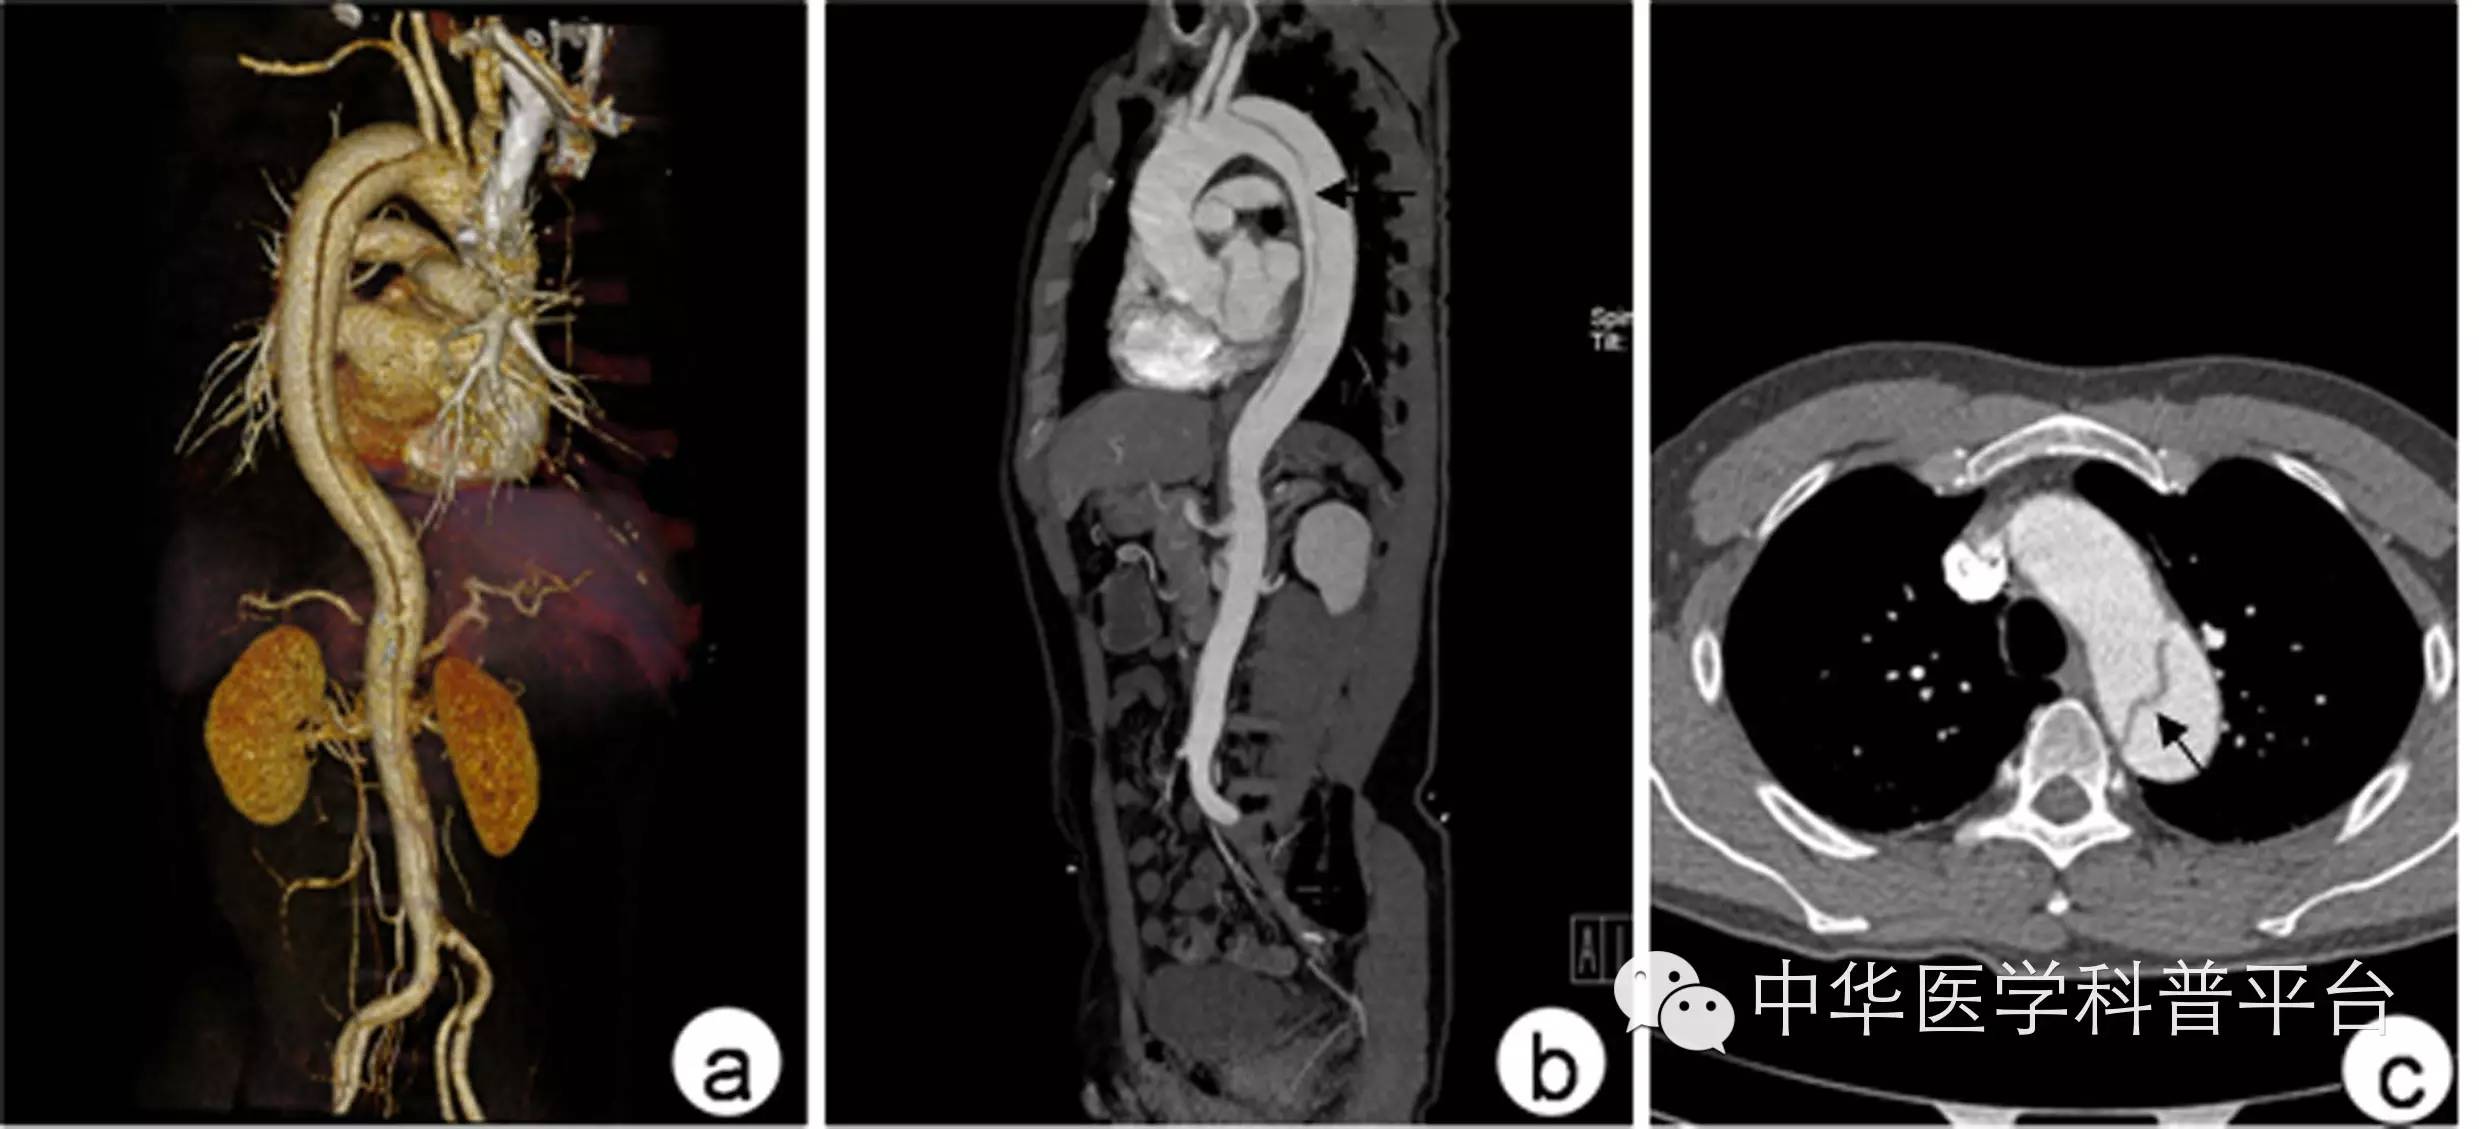

二、主动脉CTA

是目前最常用的术前影像学评估方法,其敏感性达90%以上,其特异性接近100%。CTA断层扫描可观察到夹层隔膜将主动脉分割为真假两腔,重建图像可提供主动脉全程的二维和三维图像,其主要缺点是要注射造影剂,可能会出现相应的并发症,而主动脉搏动产生的伪影也会干扰图像和诊断。